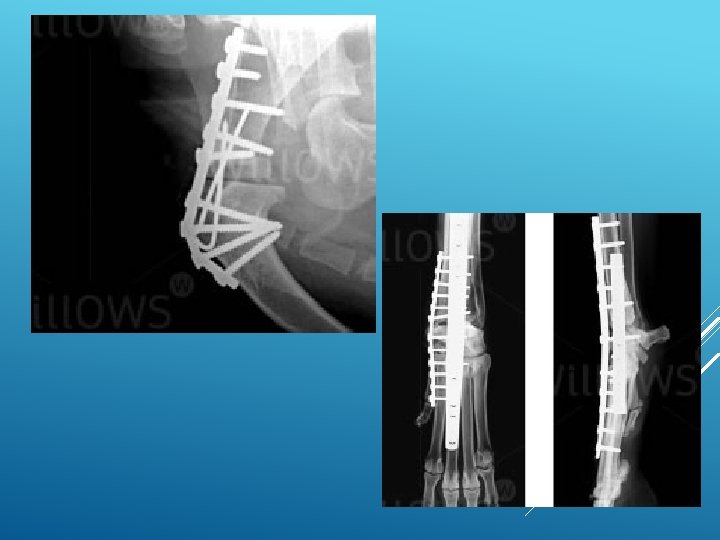

What is arthrodesis? Arthrodesis means the surgical fusion of a joint. In other words, the bones forming the joint are permanently joined together so that there is no movement in this part of the limb. Arthrodesis is a salvage procedure that is generally only performed when there are no other options to save the function of the joint.

What joints can be arthrodesed (fused)? The shoulder, elbow, carpal (wrist), stifle (knee), hock (ankle) and digit (toe) joints can be arthrodesed. The main joint that cannot be fused is the hip joint. This is generally not a problem since the hip joint can be replaced with an artificial one. Elbow and knee replacements are also possible alternatives to arthrodesis of these joints.

indications for arthrodesis are: osteoarthritis that is causing chronic pain and cannot be managed medically joint instability that cannot be treated by other means fractures involving the joint surface that cannot be repaired infection involving the joint that fails to respond to antibiotics tumours in or around joints muscle/tendon rupture that cannot be managed directly

There a number of important steps when fusing a joint: the surface of the joint (known as the articular cartilage) must be removed to enable bony fusion. a bone graft should be placed into the spaces between the bones to promote fusion. This may be an autograft (from the patient), an allograft (from a donor) or a combination of both.